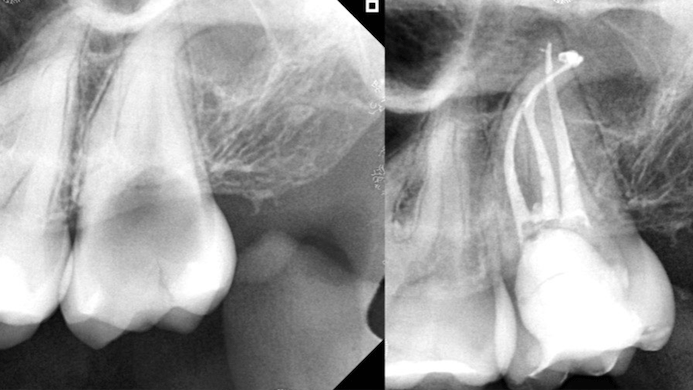

Sai lầm thường gặp khi tạo đường trượt bằng tay và cách phòng tránh Tạo đường trượt (Glide Path) là bước khởi đầu quan trọng, quyết định sự an toàn và thành công của toàn bộ quy trình nội nha. Tuy nhiên, việc thực hiện đường trượt bằng tay (thủ công) luôn là một thách